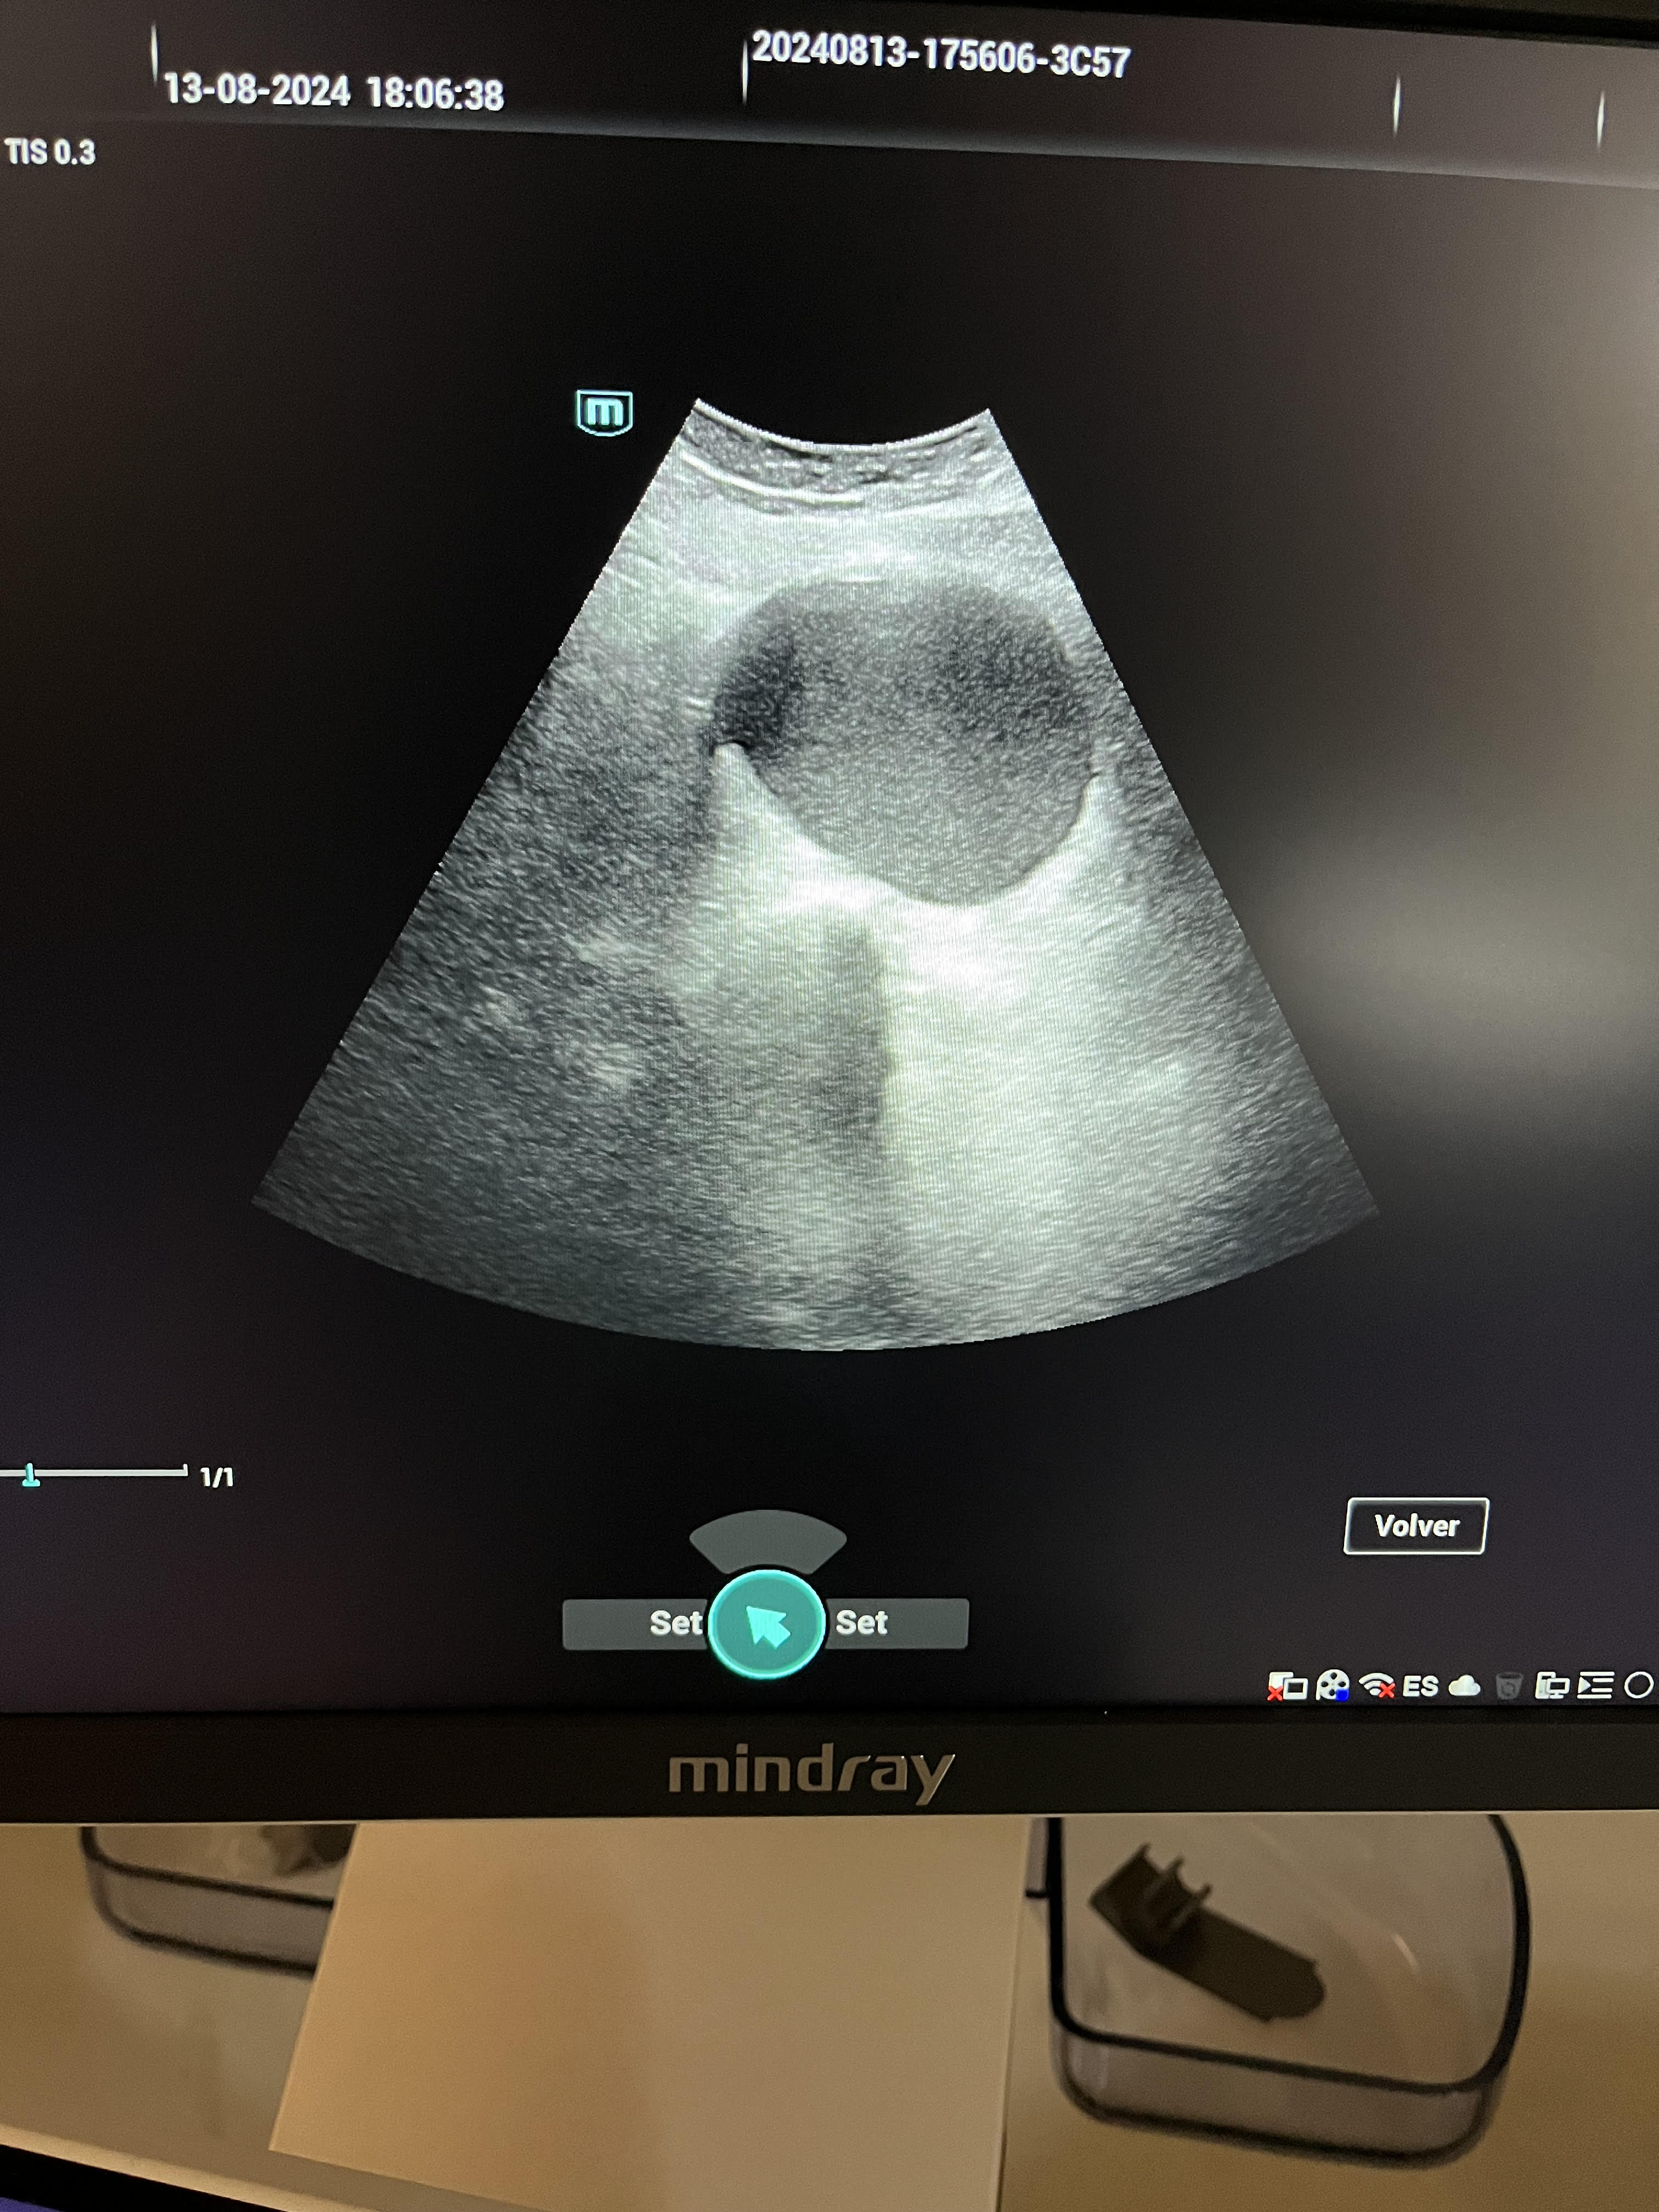

La ecografía revela un útero desplazado por una tumoración quística de contenido hipoecoico de 77 x 63 mm en el lado derecho, sin captación de señal Doppler. La anatomía uterina no se visualiza claramente, y se observa una línea endometrial irregular.

La sospecha principal fue de endometrioma, considerándose el diagnóstico diferencial con mioma uterino. En la valoración hospitalaria, se confirma el hallazgo de endometriosis.

En la valoración hospitalaria mediante ecografía ginecológica reglada, se describe un útero de 90 x 55 x 58 mm con signos de adenomiosis: asimetría miometrial (miometrio anterior de 16 mm y posterior de 33 mm), quistes de la unión miometrial y miometrio dishomogéneo. Cavidad en signo de interrogación (question mark sign), junto con quistes endometriósicos de gran tamaño a nivel axial bilateral, lo que sugiere endometriosis profunda. Se pauta tratamiento con progestágeno, a la espera de evaluar la evolución y considerar la posibilidad de una histerectomía radical con salpingooforectomía bilateral.